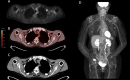

Background: mRNA COVID-19 vaccines are known to provide an immune response seen on FDG PET studies. However, the time course of this metabolic response is unknown. We here present a temporal metabolic response to mRNA COVID-19 vaccination in oncology patients undergoing standard of care FDG PET.

Methods: 262 oncology patients undergoing standard of care FDG PET were included in the analysis. 231 patients had at least one dose of mRNA COVID-19 vaccine while 31 patients had not been vaccinated. The SUVmax of the lymph nodes ipsilateral to the vaccination was compared to the contralateral to obtain an absolute change in SUVmax (ΔSUVmax).

Results: ΔSUVmax was more significant at shorter times between FDG PET imaging and COVID-19 mRNA vaccination, with a median ΔSUVmax of 2.6 (0-7 days), 0.8 (8-14 days), and 0.3 (> 14 days), respectively.